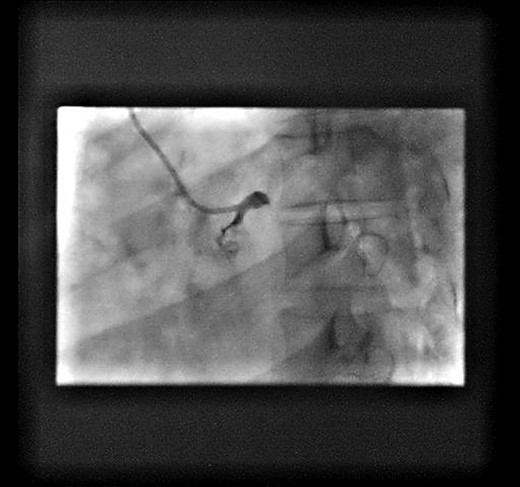

At the beginning of the procedure, the left main stem was engaged, however dampened pressure was noted and a test shot showed left main stem occlusion with dissection (Fig. 1).

Test shot showing left-main-stem occlusion with dissection (National-Heart-Lung and Blood-Institute class F).